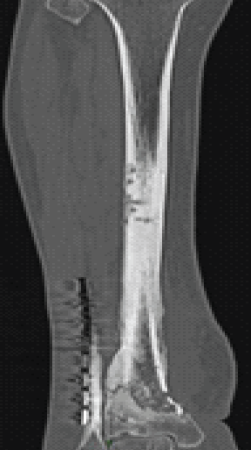

Radiological assessment (radiograph, computed tomography-scan, and magnetic resonance imaging) showed osteitis of the distal tibia over an area of 9 cm (Figs. 2 and 3).

Figure 3: Pre-operative computed tomography scan showing the extent of osteitis in the distal tibia over 9 cm.